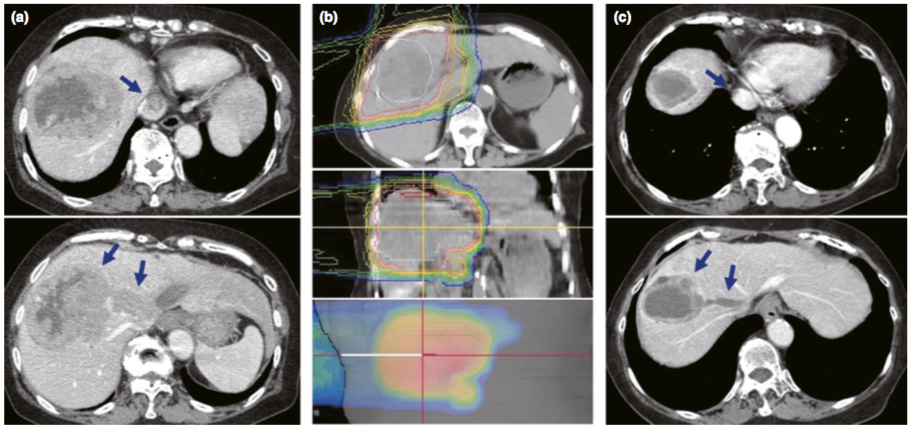

81岁女性,晚期HCC的CT图像,IVC中可见大量肿瘤血栓。PBT前(a)、PBT期间(b)、PBT完成后2个月(c)的CT图像。PBT后,肿瘤和肿瘤血栓均显著消退(箭头)。等高线:红线,等剂量为90%;蓝线,等剂量为10%。HCC,肝细胞癌;IVC,下腔静脉;PBT,质子治疗。(图片来自参考文献2)